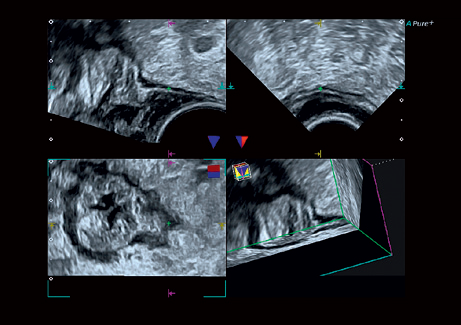

• MPR - функция мультипланарной реконструкции для визуализации исследуемой области в 3-х ортогональных плоскостях

MPR:

Да